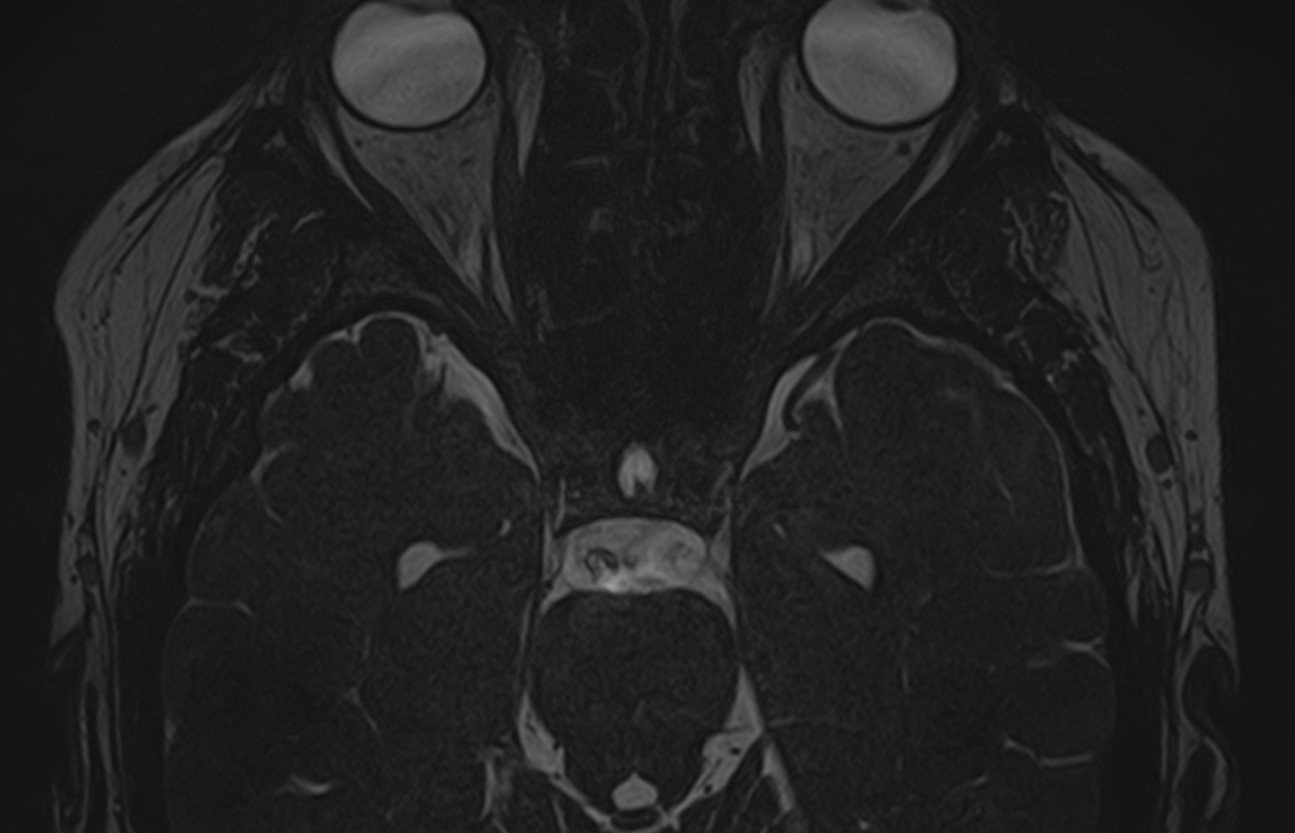

Для диагностики поражения черепно-мозговых нервов, а также оценки состояния окружающих их тканей и визуализации сосудистой сети головного мозга в клинике «Доступная медицина» проводится комплексное обследование МРТ головного мозга + Мр-ангиография головного мозга + МР-венография головного мозга + черепно-мозговые нервы. Данное обследование включает в себя несколько протоколов: стандартный – для оценки состояния всех структур головного мозга и дополнительные – для изучения очагов поражения черепных нервов и визуализации всей сосудистой системы головного мозга.

Исследования выполняются на современном высокопольном томографе экспертного класса TOSHIBA VANTAGE TITAN 1,5 Тесла, который использует разные режимы сканирования с толщиной среза от 1мм в различных плоскостях с последующей цифровой обработкой полученных данных для создания трехмерных изображений. МР-ангиография отображает состояние артериальной системы кровоснабжения головного мозга. МР-венография головного мозга позволяет детально изучить особенности венозного русла головного мозга.

Компьютерная программа обрабатывает данные, полученные при сканировании, и формирует объемные изображения как самого мозга, так и сосудистой системы в отдельности без прилегающих тканей. Методики применяются одновременно и взаимодополняют друг друга.

Данное комплексное исследование в большинстве случаев проводится с контрастным усилением, которое необходимо для улучшения визуализации черепно-мозговых нервов. Для этого внутривенно вводится препарат, содержащий гадодиамид (соли металла гадолиния) для получения изображений с высокой четкостью и контрастностью, что способствует ранней диагностике заболеваний головного мозга.